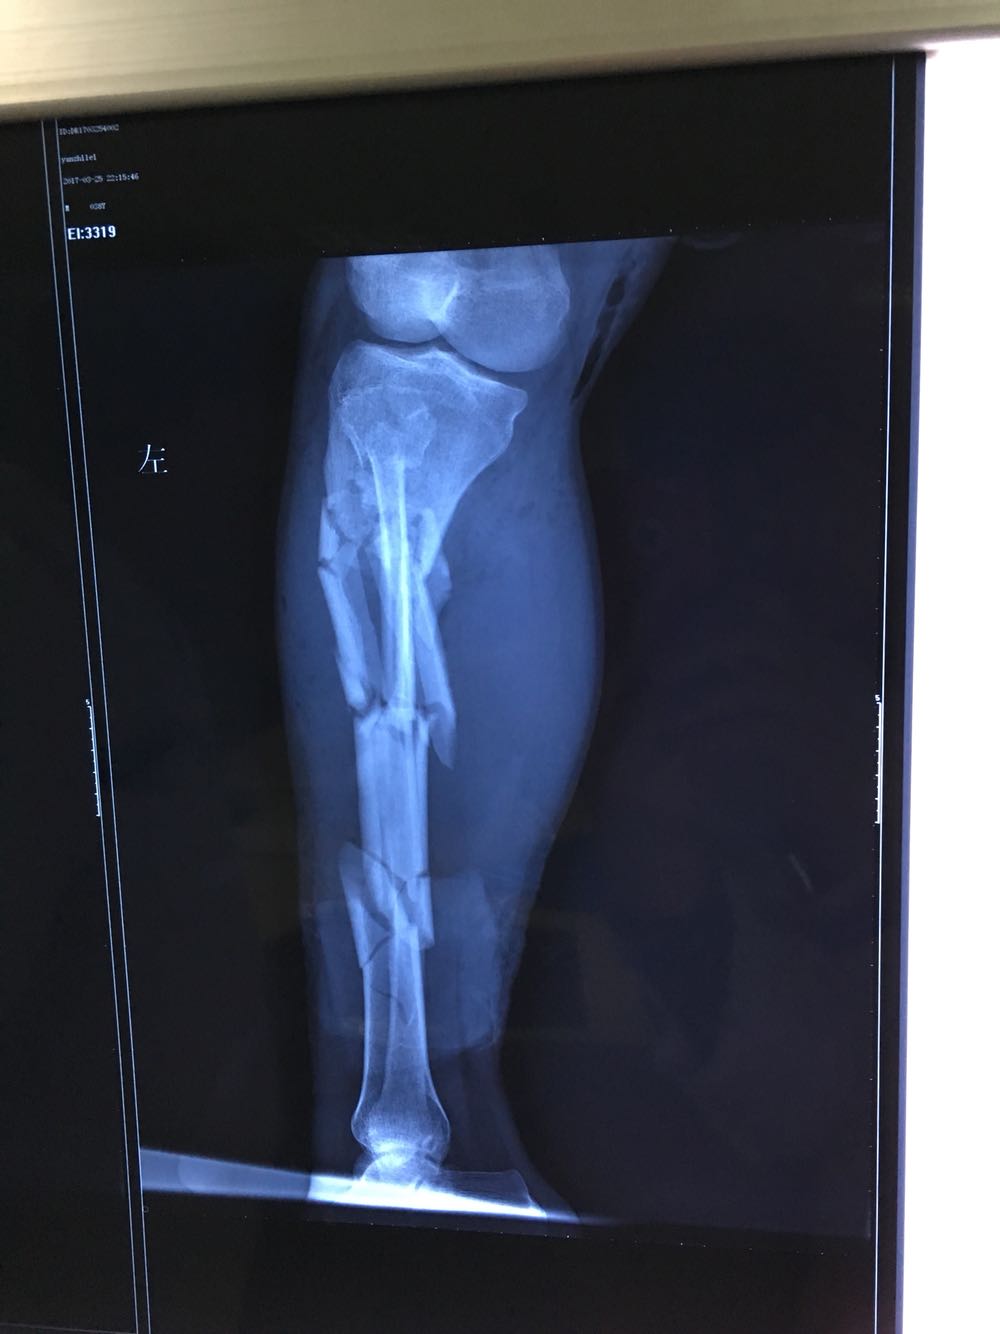

患者男性,38岁,主因双下肢外伤疼痛出血0.5小时来诊。既往病史无特殊。

血压105/60mmHg,心率110次/分,面色苍白,痛苦面容。心肺腹查体无异常。

双下肢开放性骨折 多脏器功能不全 入院后立即给予补液抽血补充血浆及红细胞,完善术前检查,左下肢减张固定,右下肢跖跗关节远端离断。术后患者转至上级医院进一步治疗!